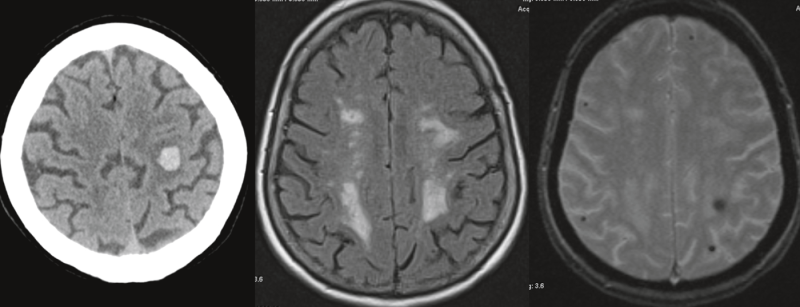

• This content is machine translated Microangiopatía cerebral y demencia vascular

Pequeñas embarcaciones de gran importancia

La demencia vascular (DV) es la segunda causa más común de demencia después de la demencia de Alzheimer y, por tanto, la forma no neurodegenerativa más común de demencia. No…